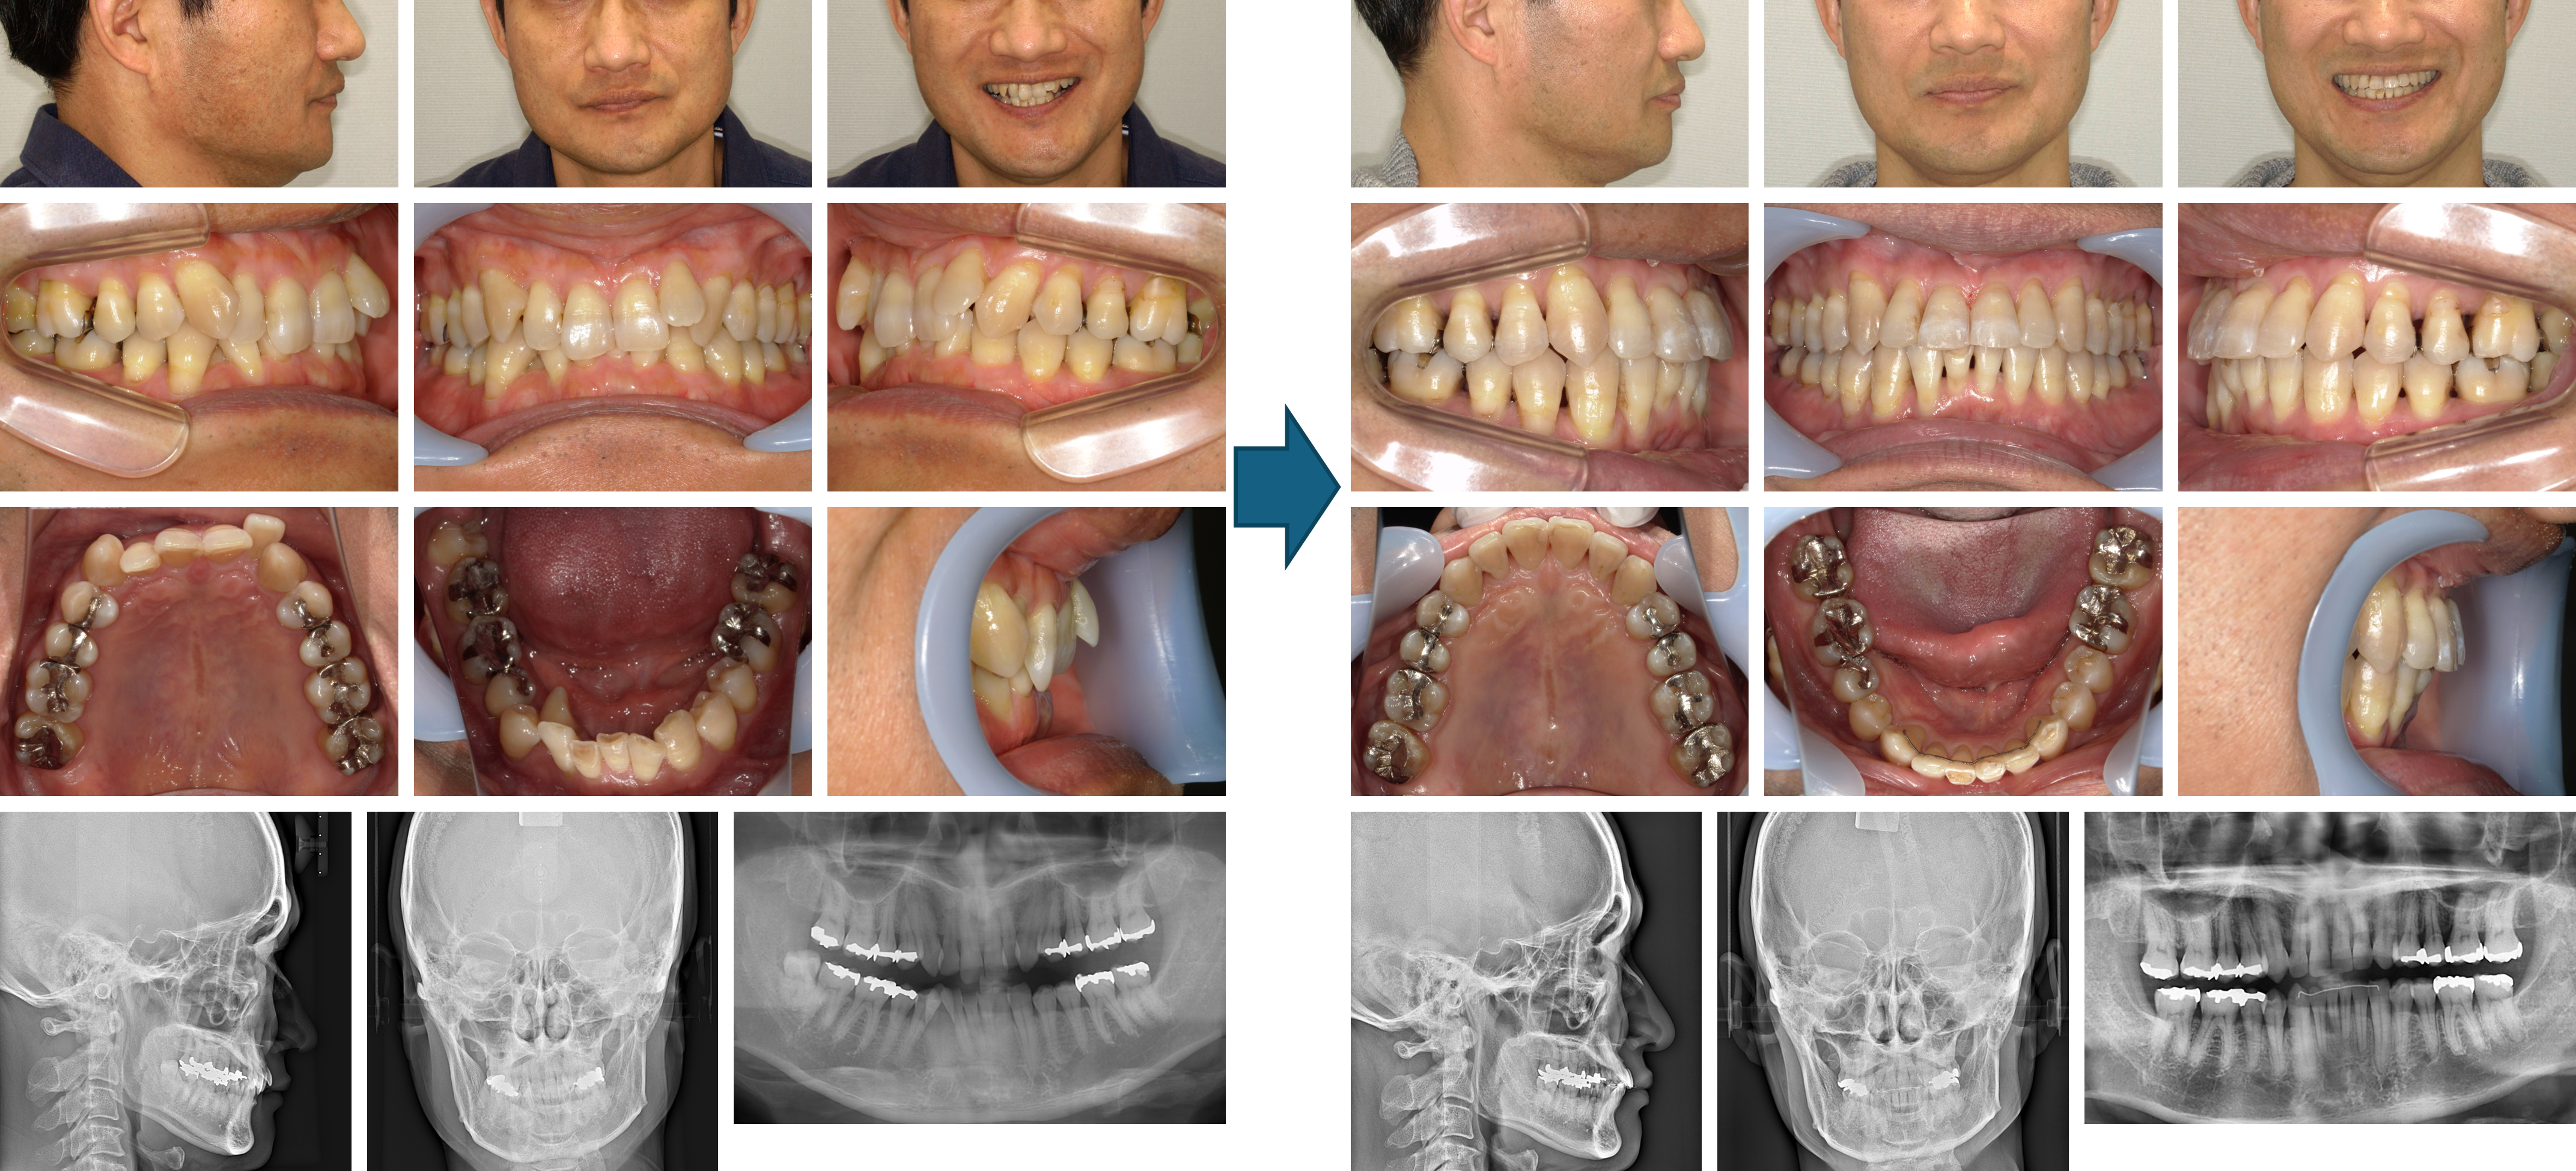

【治療例】初診時年齢:15歳2か月 / 性別:男性 / 主訴:上の前歯が出ている

症例の概要:上顎前歯の唇側傾斜によって口唇閉鎖時は上唇の突出とオトガイの過緊張が認められました。最初に上顎の抜歯を行い、下顎の抜歯は治療経過から考慮することを患者さんにお伝えして治療を開始しました。結果、下顎は一部の歯の隣接面を削ったが抜歯をせずに顔貌の改善および緊密な咬合を獲得することができました。

主訴:上の前歯が出ている

診断名: 著しく上顎前歯が唇側傾斜した下顎後退型の骨格性Ⅱ級、ローアングル症例

使用した主な装置: マルチブラケット装置(金属)、サービカルヘッドギア、顎間ゴム

抜歯/非抜歯および抜歯部位: 右上4番8番、左上4番、右下8番の抜歯

治療期間:2年9か月

治療回数:38回

リスクの副作用:歯の移動、装置による口内炎、抜歯などの痛みや歯肉退縮、歯根吸収、後戻りなどの可能性がある